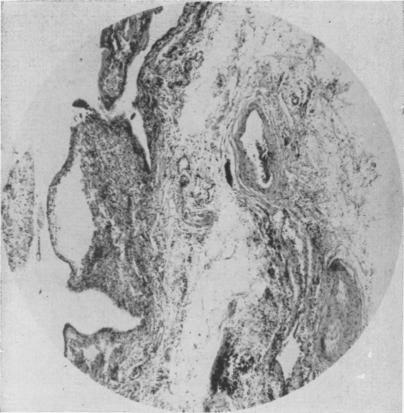

Choledochoduodenal fistula: its surgical management, including a report of three cases.

Ann Surg. 1954 Apr;139(4):510-6. doi: 10.1097/00000658-195404000-00018.